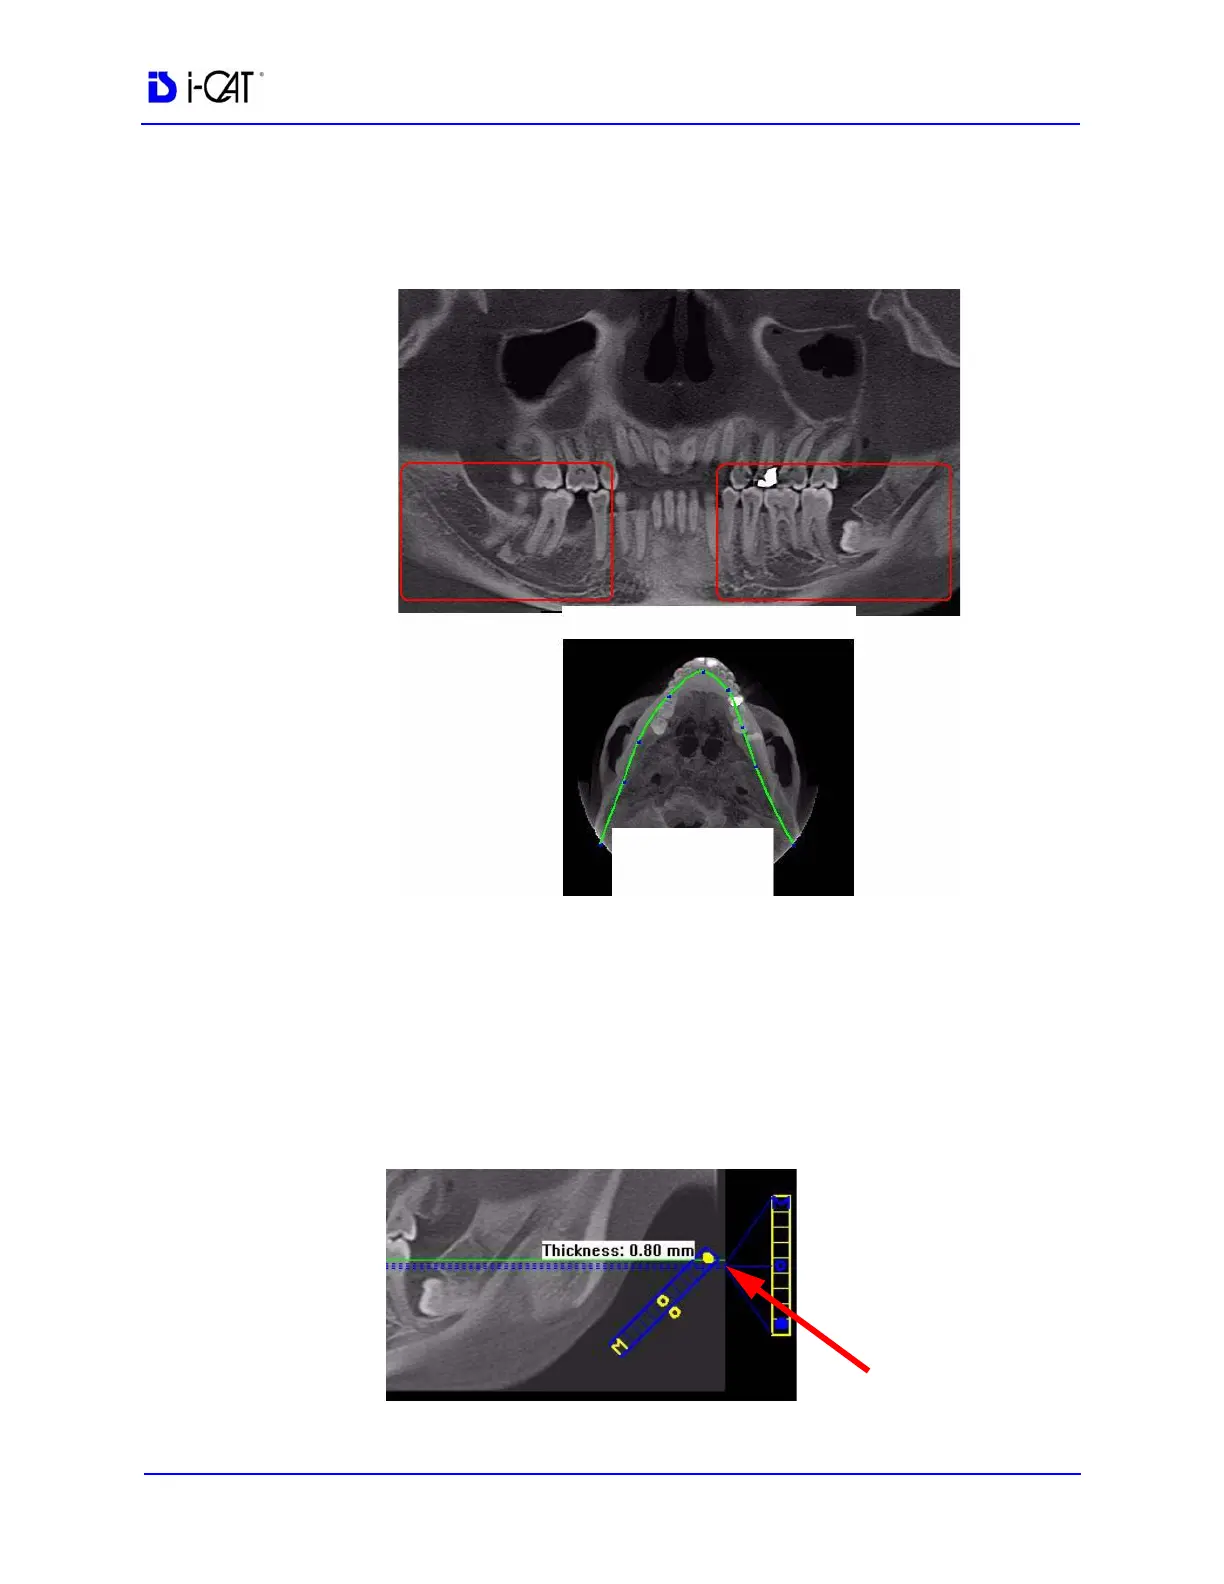

2. On the axial view, click and drag the blue dots on the contourline

as needed to bring the nerve canal(s) into view on the

panoramic view.

3. Double-click the panoramic view image to display the Implant

Planning screen.

4. On the panoramic map view, click the solid dot on the diagonal

slice control to check the slice thickness. If thickness is over 1.0

mm (1.2 mm for voxel sizes greater than or equal to 0.3 mm),

drag the solid dot down to reduce the slice thickness. Slice must

be no thicker than stated above to be able to mark points in the

panoramic map view.